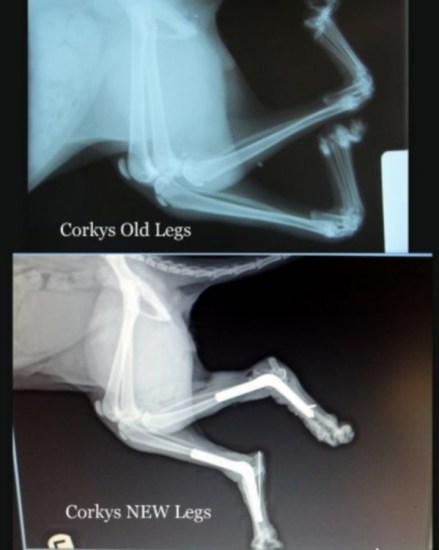

To give you an idea of the severity of Corky’s condition, here’s a before and after X-Ray from CATS Cradle.

Getting Corky’s legs flipped around was no simple feat. The surgery was carried out on April 5 by Dr. Dan Burchill, who used a technique employed to solve a similar problem with dogs. It took five hours of surgery to not only turn Corky’s legs, but reinforce them with steel pins. Burchill also had to cut Corky’s achilles tendon, in order for the cat’s toes to unclench and spread apart.